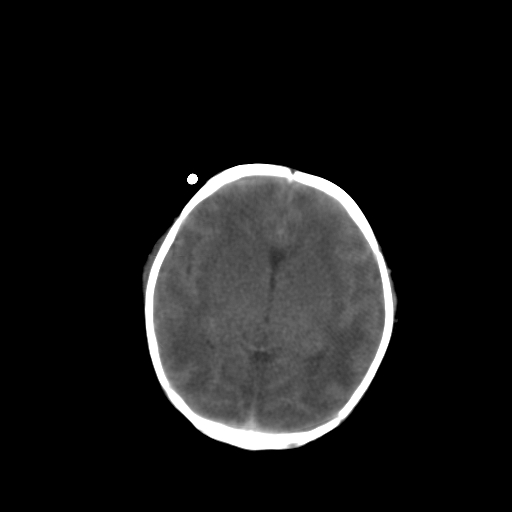

男,2天,孕31周早产儿,出生后窒息3分钟,精神反应差。

脑实质弥漫低密度,灰白质界限不清:结合临床考虑重度hie

孕31周的表现跟这差不多,但临床有窒息史,有症状,支持考虑hie